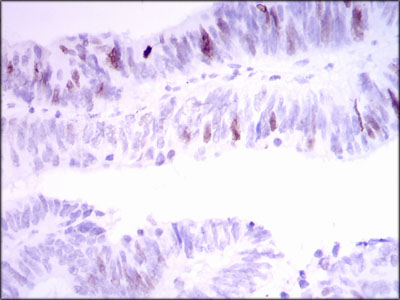

Immunohistochemical analysis of paraffin-embedded human cervical cancer tissue using anti-INCENP antibody. Counter stained with hematoxylin.

Immunohistochemical analysis of paraffin-embedded human rectum cancer tissue using anti-INCENP antibody. Counter stained with hematoxylin.